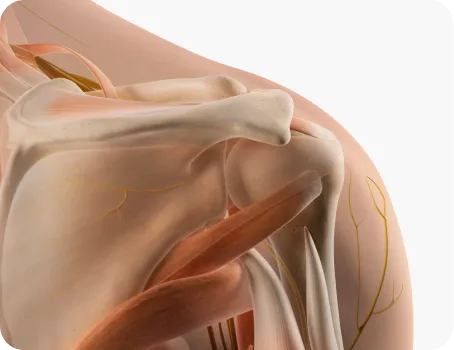

스포츠 재활 도수치료

스포츠 재활 전문 물리치료사의 정확한

근력 측정과 기능적 움직임 평가를 통해

통증을 치료하고 근력과 관절 가동범위를 회복하여

치료의 만족도를 높입니다.

수술 후 재활 도수치료

의사와 물리치료사의 충분한 논의 후

수술 봉합 부위 유착으로 인한 관절가동범위

제한을 풀어주고 통증이 발생하지 않도록

재활을 진행합니다.

예를 들어, 어깨 후면부 통증의 경우 마사지는 능형근, 광배근, 승모근 등 표면 근육을 푸는 데 집중합니다.하지만 도수치료는 경추 디스크 탈출, 사각근의 신경포착, 근육 문제, 견관절 가동범위 제한 등 다양한 원인을 파악하고 그에 맞는 치료를 제공합니다. 이러한 전문성 때문에 마사지는 일반인도 할 수 있지만, 도수치료는 국가가 인정한 물리치료사 면허를 가진 전문가만이 시행할 수 있습니다.